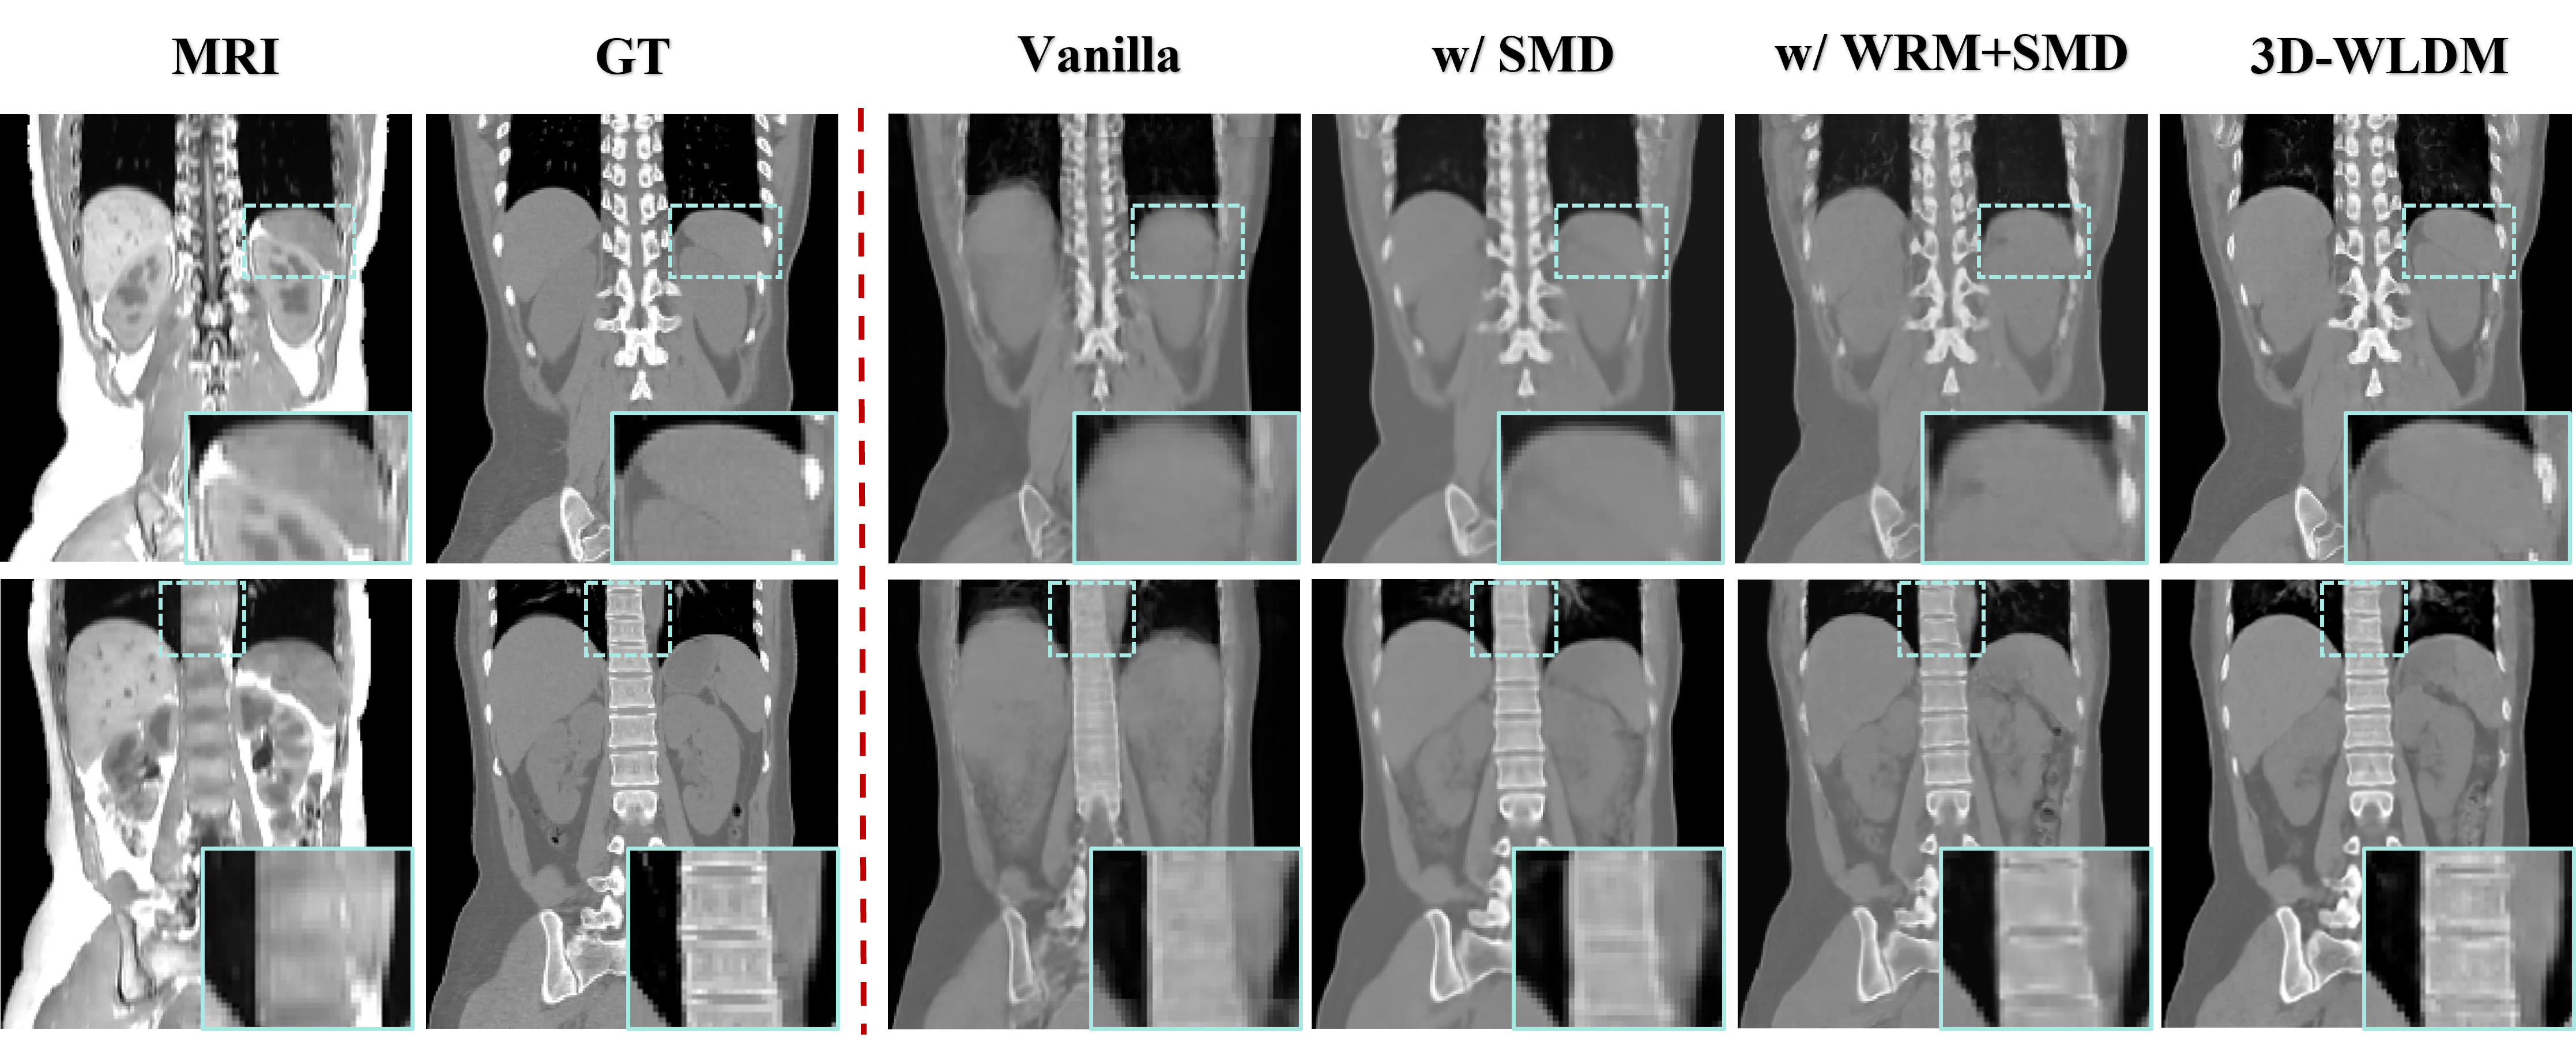

To examine the contribution of each model component within 3D-WLDM framework, we performed a series of ablation experiments, as detailed in Table II. The Vanilla model serves as the baseline, employing a standard 3D latent diffusion framework in which the MR latent representation is concatenated with Gaussian noise to form a dual-channel input, without any explicit structural or modality-specific enhancements.

Introducing SMD into the baseline enhances the model’s ability to preserve anatomical structure during the generative process. By decoupling structural information from modality-specific features during pretraining, the model learns to anchor geometry consistently across the diffusion trajectory. While this improves overall spatial alignment, some fine-grained details remain suboptimal.

Incorporating WRM further improves image reconstruction by enhancing the representation of high-frequency features. Through wavelet-domain processing, WRM enriches the encoding and decoding between the image and latent spaces, yielding more precise recovery of complex anatomical structures, particularly in osseous regions.

The full model, combining WRM, SMD, and DSCA achieves the most robust performance across all evaluated metrics. DSCA reinforces the interaction between structural and modality-specific signals in the latent space, enabling the network to generate synthetic CT volumes with enhanced stability contrast, reduced artifact. Relative to the baseline, the full model improves PSNR by 2.31 dB, SSIM by 0.23, and reduces MAE by 28.08, underscoring the cumulative benefit of the proposed modules.

These quantitative findings are further supported by the qualitative results in Fig.7. The Vanilla model generates synthetic CT images with perceptual quality comparable to StableDM-3D (Fig.5), yet fails to capture modality-specific transformations with sufficient structural fidelity, particularly in anatomically complex 3D regions where spatial encoding is inherently more challenging.

Introducing SMD leads to more accurate anatomical alignment by explicitly preserving structure throughout the diffusion process. Organ and tissue boundaries become more coherent, though finer anatomical details remain underrepresented. The addition of WRM markedly improves the synthesis of high-frequency features, especially in regions with intricate bone morphology such as the vertebrae and ribs, by leveraging wavelet-domain encoding to reinforce multiscale structural representation.

The full model further benefits from the integration of DSCA, which refines the fusion of structural and modality cues and enhances both generation stability and contrast accuracy. As shown in Fig. 7, this results in improved delineation of abdominal organs, such as the stomach and kidneys, with sharper boundaries and more realistic texture.

Collectively, these findings substantiate our central hypothesis: that explicit disentanglement of structure and modality, combined with multiscale encoding and attention-guided feature fusion, is critical for achieving accurate, high-quality 3D medical image synthesis in cross-modality tasks.